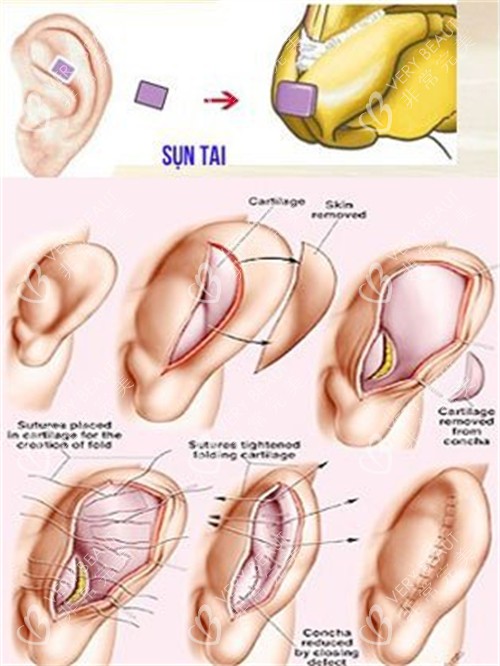

当时,医生跟我介绍说,用自己的肋骨隆鼻,材料取自自身,不会有排异反应,结果也会很自然。我心动不已,毫不犹豫地就做了手术。

我赶紧去医院询问医生,医生告诉我,这是肋骨鼻吸收的正常现象。原来,肋骨在植入鼻子后,会有一定程度的吸收,每个人的吸收情况不同,我的吸收情况相对明显一些。